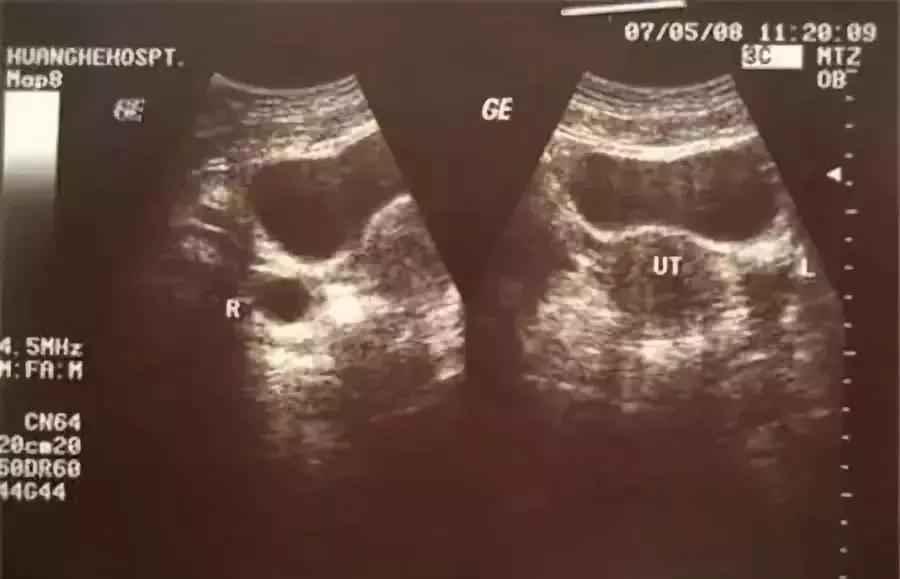

测量基础体温来监测太麻烦也影响睡眠,排卵试纸又不能准确测到排卵时卵泡的大小,采用B超监测排卵是最好的,这种方法可以准确的知道排卵的时间、排卵时卵泡的大小、排卵时内膜的厚度和形态。

一般在月经周期第10天左右开始监测,观察卵泡直径的变化,在排卵前4天的卵泡直径平均每天约增3mm,在排卵前卵泡成熟约18-25mm,排卵后卵泡消失,连续监测可见在排卵前卵泡不断长大,当最大的卵泡消失时,提示发生排卵。

第2次B超:在月经第10天左右,可以看到1-2个优势卵泡,并能计算卵泡生长的速度。

第3次B超:月经第13天左右,恰恰在排卵前,这时B超会出现卵泡周围透声环,有经验的医生会告诉你,卵泡应该在24小时内排卵。

第4次B超:刚刚排卵后第14天左右,卵泡已经消失或显著缩小5mm以上,子宫直肠隐窝内可见液性暗区4-6mm,甚至更多。